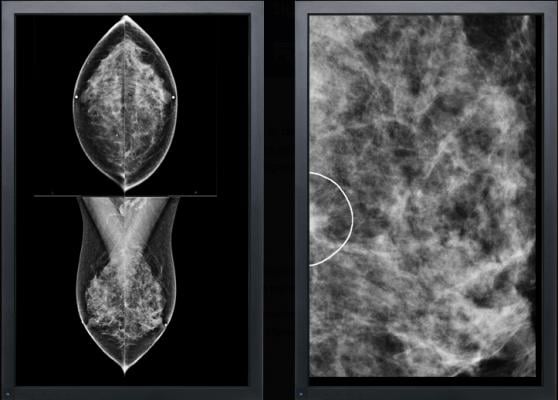

February 6, 2014 — VuComp received U.S. Food and Drug Administration (FDA) premarket approval (PMA) of the M-Vu CAD Version 3 system for digital mammography. This generation of CAD technology intends to lower false positive rates. The company upgraded all M-Vu users’ systems with M-Vu CAD Version 3 at no charge.

The M-Vu CAD system uses advanced computer vision algorithms to identify areas of a mammogram that are consistent with breast cancer. M-Vu CAD Version 1 met the FDA-recommended reader study standard for proving the effectiveness of mammography CAD.

The key advancement of the new M-Vu CAD is its reduction of false positive marks for breast cancer.

Version 3 is capable of 97 percent sensitivity for microcalcifications and 87 percent sensitivity for masses. Total false positive rates measure at 0.26 marks per image (1 false positives per four-view study).